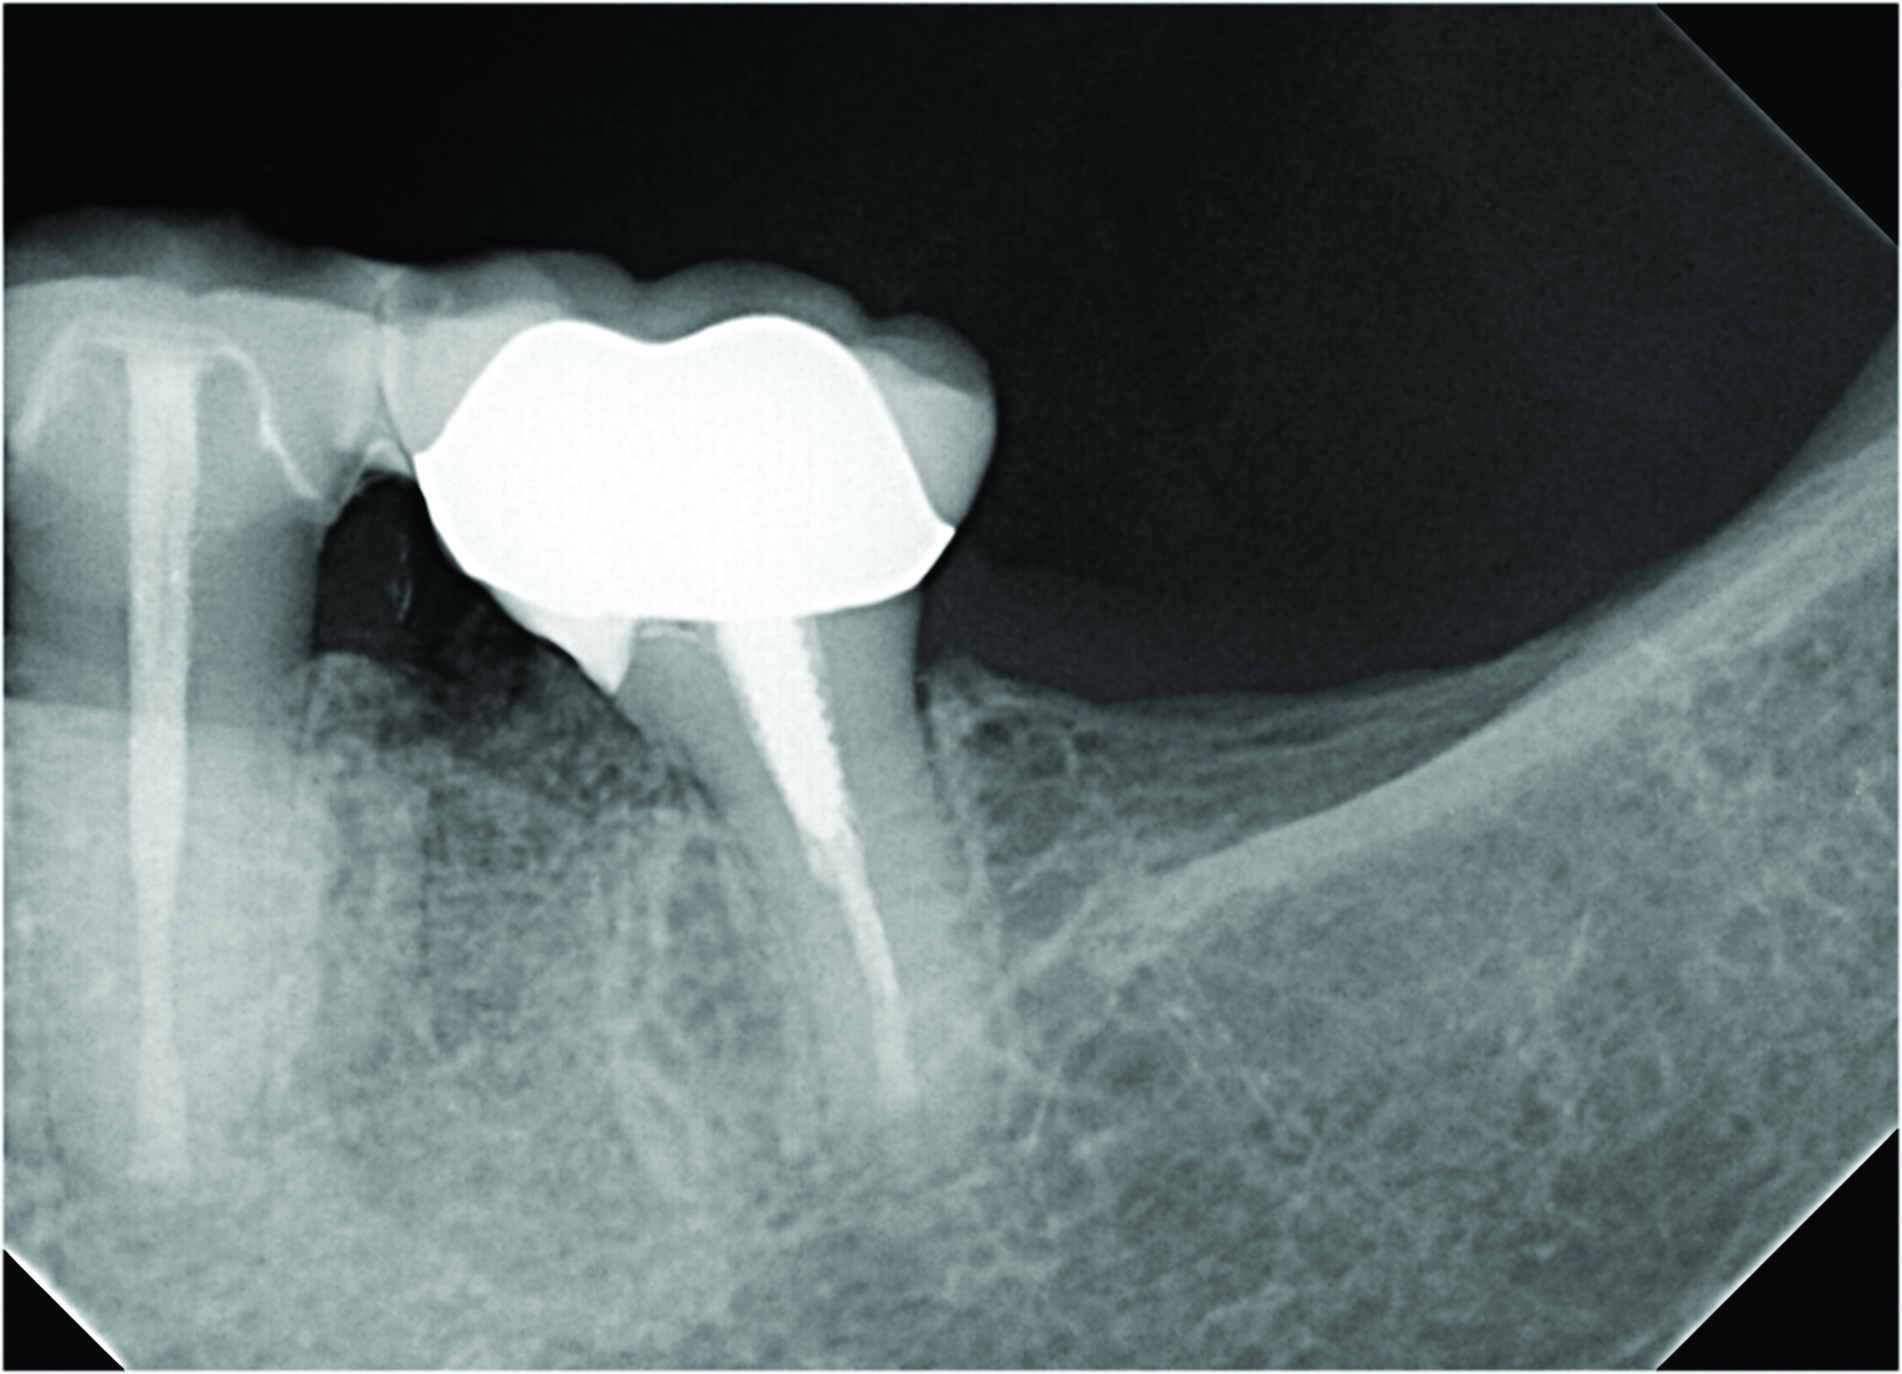

A number of treatment factors must be considered and certain objectives accomplished in order to create a cleansable tooth. Starting with the resection of the root, there can be no residual root stub remaining so that a furcation does not persist. The most cleansable shape after resecting a root is achieved by removing the root such that a smooth, flowing angle of departure exists from the retained root to just below the contact space with the adjacent tooth, as can be seen in Figure 6. In many cases this may result in an esthetic compromise; however, if the cantilevered portion of the tooth is flat or creates an uncleansable trap for bacteria to accumulate, the case will have an elevated risk of developing recurrent decay and increased crestal bone loss over time. The importance of preventing a plaque trap via a cleansable shape typically outweighs the esthetic compromise. While achieving this objective can be technically difficult, especially on the lingual side of mandibular molars and on the mesiopalatal aspect of maxillary molar mesiobuccal root resections, it is a crucial step in the surgical process.

Figure 6, which shows a clinical image of a tooth No. 14 with a mesiobuccal root resection, highlights the desired cantilever contour result. Note that no root stub exists and the cantilever flows smoothly to the retained palatal and distobuccal roots and progresses mesially to a point below the contact space with the adjacent tooth.

During the resection process, directly visualizing the smooth transition to the retained distobuccal and palatal roots is essential and made possible by utilizing an operating microscope. Note that in Figure 6 the underside of the tooth has been restored with a resin-modified glass-ionomer (RMGI) restorative material. The restoration of the underside of the remaining tooth is important to satisfy the objective of a maximally cleansable result. A new restoration to seal the underside of the cantilevered section of the tooth will almost always be needed, except in the few cases where the resection of the root and shaping of the cantilevered section results in the exposure of a perfectly smooth existing restoration with no voids. Most core buildups do not extend into the root canal orifices far enough to satisfy this condition, however, which is why placing a new restoration on the underside of the cantilevered portion should be planned in almost every case. An additional benefit of placing a new restoration that covers much of the cantilevered underside of the tooth is that the underside of the tooth will become more resistant to decay since the restorative material itself cannot directly decay.

Figure 7 shows an example of a mesial root resection that satisfies the objective of creating a smooth contour from the distal root toward the contact space on the mesial aspect, with no overhang, especially toward the lingual side of the root. This image also demonstrates an appropriate restoration placed to seal the underside of the cantilevered portion of the root.

As clinically observed by the authors, most root resection cases in which a graft is placed (see "Graft Placement" below) will heal over time with the crestal bone stabilizing at a point that is 1 mm to 3 mm below the cantilevered portion of the tooth. This fact reinforces the importance of having a more coronal resection level and not leaving a stub of the resected root; a stub will extend further apically and over time result in greater crestal bone loss and future problems related to plaque control and periodontal issues. The case shown in Figure 8 is a 5-year post-treatment image of tooth No. 30, depicting the anticipated healing outcome of a grafted resected root socket. It demonstrates the result of well-managed plaque control and optimally maintained crestal bone.

Fig 5. A cleansable resected root surface, the root filling, and the root contour will affect the prognosis. Fig 5: Tooth No. 19 at 1-year post-treatment with a remaining stub of the mesial root following root resection; note a subsequent larger-than-expected crestal bone loss defect below the cantilevered portion of the tooth. Incomplete resection and lack of proper contour toward the mesial contact has created a plaque trap and subsequent unstable periodontal status. This problem can be avoided with a more aggressive resection to ensure a cleansable situation. Fig 6: Clinical image of tooth No. 14 with a resected mesiobuccal root and RMGI restoration of the underside of the tooth. The resultant contour has no lips or ridges and has a smooth transition to the mesial contact space; there is also a smooth transition to the remaining distobuccal and palatal roots, creating a cleansable situation. Fig 7: Tooth No. 18 immediately following resection of the mesial root demonstrates a contoured mesial surface that smoothly blends to the mesial contact region. The underside of the cantilevered portion of the tooth is restored with a RMGI restoration, and the socket is grafted with an allograft.

Fig 8: Tooth No. 30 with a resected mesial root and restoration of the underside with a RMGI restoration at 5 years post-treatment is displaying the expected healing pattern of the crestal bone following grafting of the socket. The proper resection and contouring permits adequate maintenance and resultant stability of the tooth.

Fig 6. A cleansable resected root surface, the root filling, and the root contour will affect the prognosis. Fig 5: Tooth No. 19 at 1-year post-treatment with a remaining stub of the mesial root following root resection; note a subsequent larger-than-expected crestal bone loss defect below the cantilevered portion of the tooth. Incomplete resection and lack of proper contour toward the mesial contact has created a plaque trap and subsequent unstable periodontal status. This problem can be avoided with a more aggressive resection to ensure a cleansable situation. Fig 6: Clinical image of tooth No. 14 with a resected mesiobuccal root and RMGI restoration of the underside of the tooth. The resultant contour has no lips or ridges and has a smooth transition to the mesial contact space; there is also a smooth transition to the remaining distobuccal and palatal roots, creating a cleansable situation. Fig 7: Tooth No. 18 immediately following resection of the mesial root demonstrates a contoured mesial surface that smoothly blends to the mesial contact region. The underside of the cantilevered portion of the tooth is restored with a RMGI restoration, and the socket is grafted with an allograft.